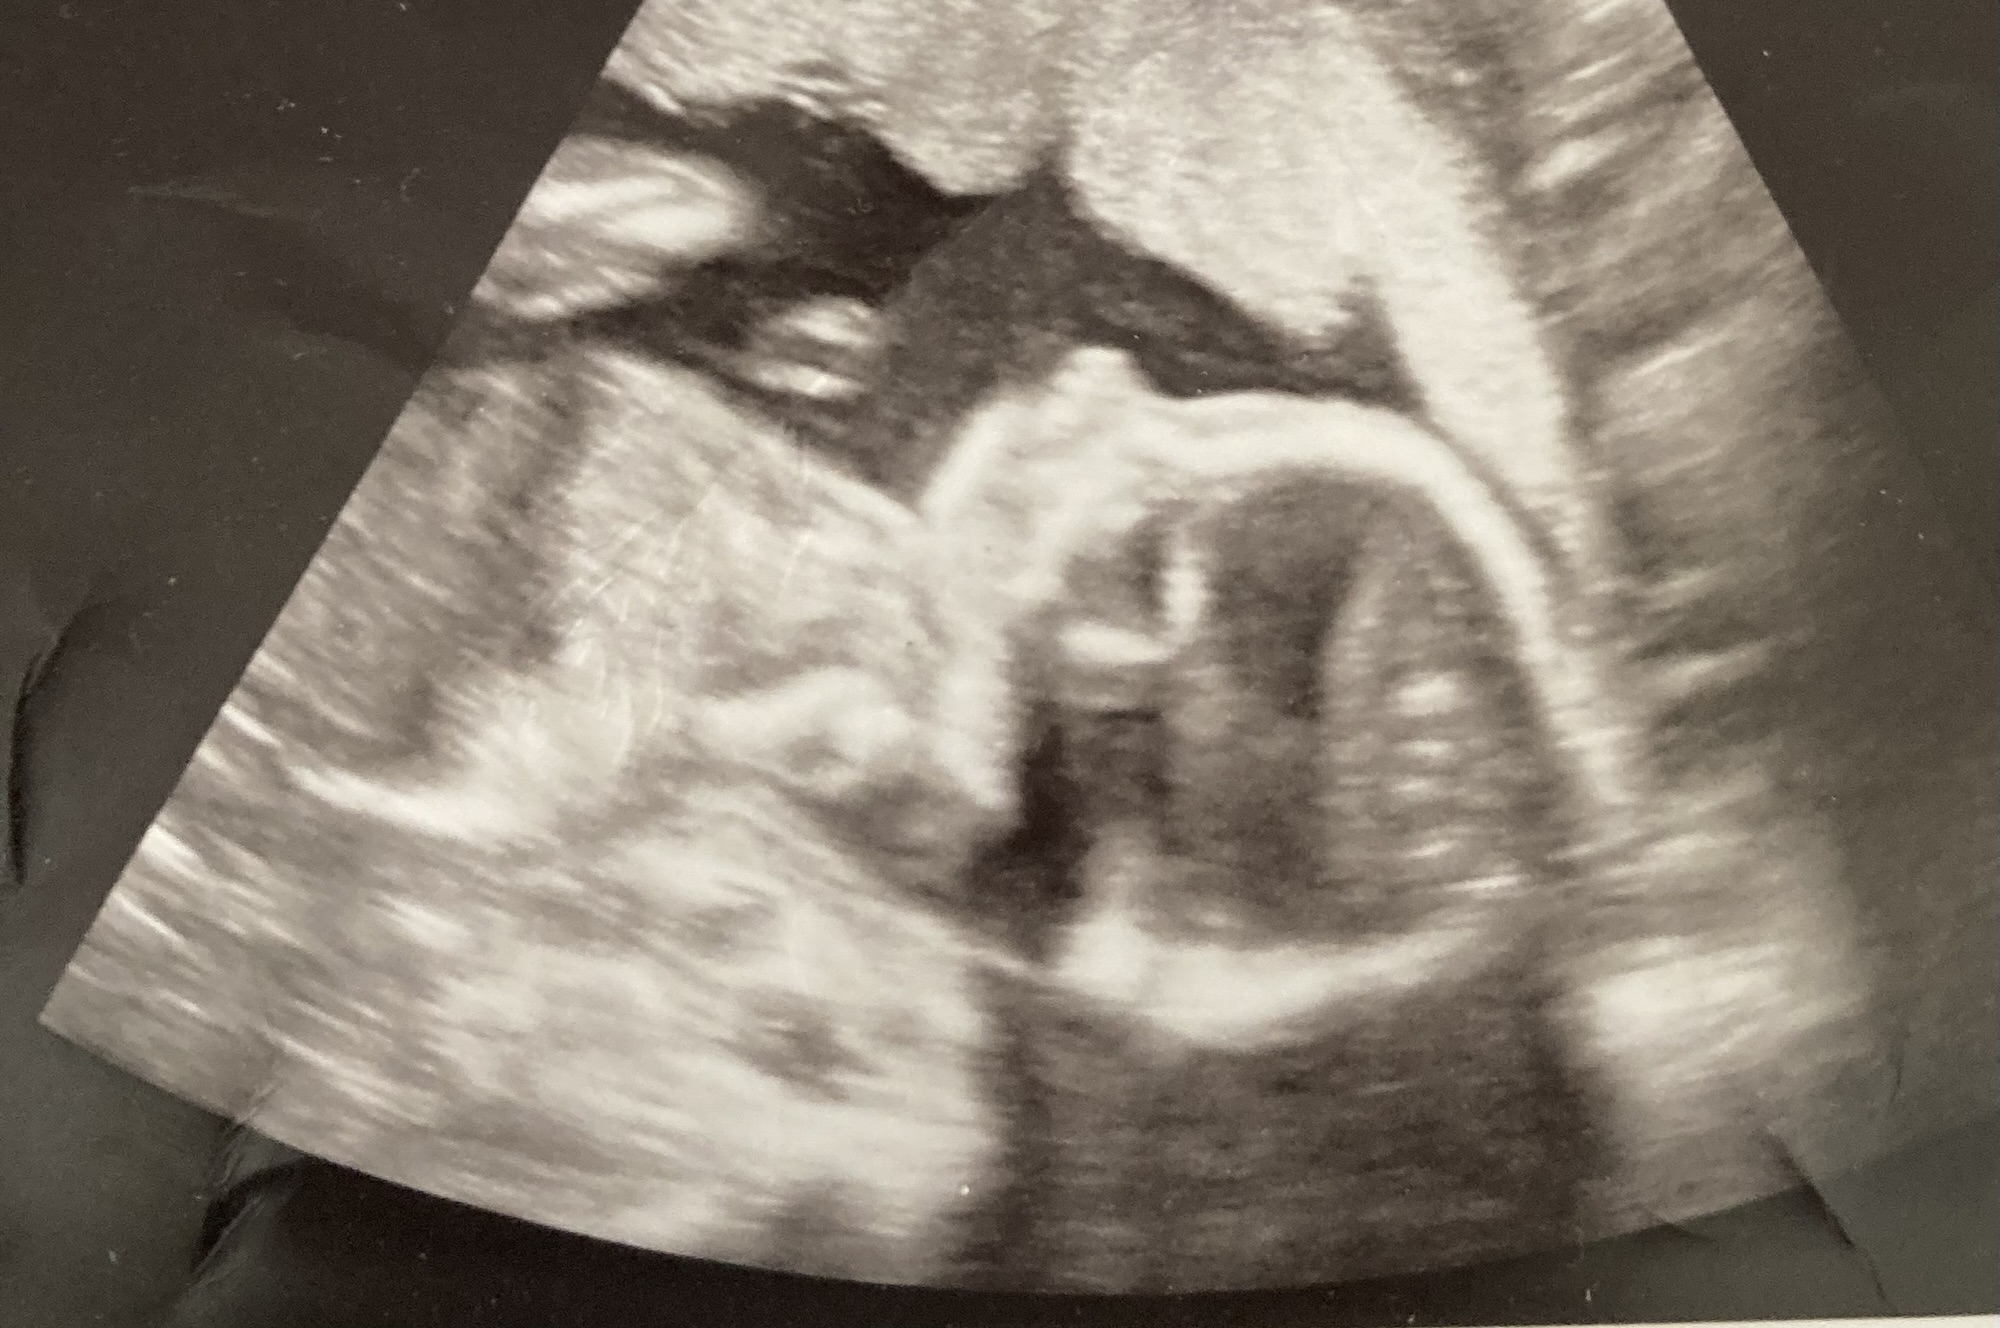

I am pregnant and have breast cancer

Having breast cancer while being pregnant has been one of my life’s greatest challenges so far. It has been extremely overwhelming to say the least. On top of receiving chemo treatments, undergoing surgeries and attending appointments, I also am parenting a wild toddler, maintaining and caring for my marriage, and keeping two dogs alive.